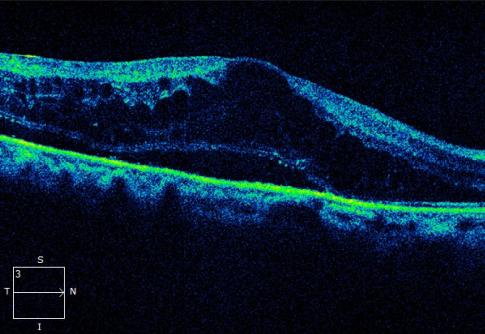

光学相干断层扫描(OCT) :可精确测量黄斑区的厚度和水肿程度

正常黄斑 OCT表现